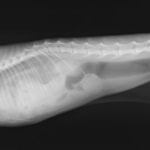

術前レントゲン

腹部臓器が胸腔内に脱出し、腹部と胸部の境界および心臓や肺の陰影が不明瞭になっています。また、胸腔内に消化管のガス陰影が認められます。